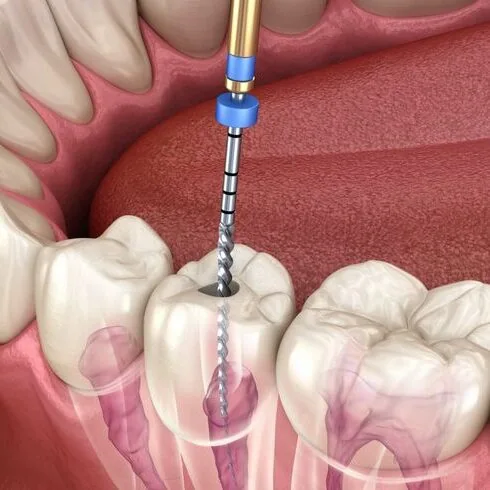

Root Canal Treatment

A common dental procedure that helps preserve natural teeth by addressing infection or damage within the tooth structure.